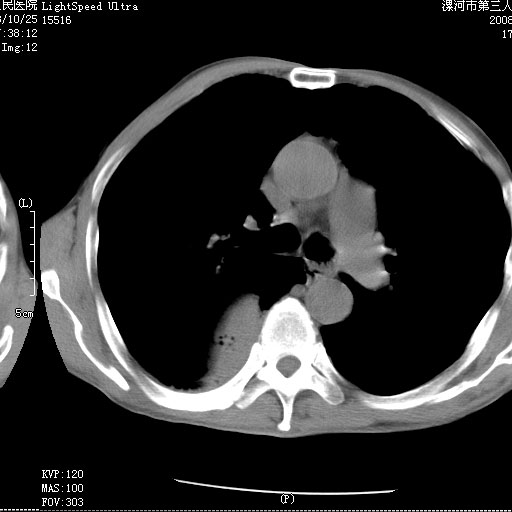

m 老年 发烧、呼吸困难,慢支、肺气肿多年;记的那次是下午大概17:38做的,晚上窒息死亡。

上面的层面就慢性支气管炎肺气肿、肺大泡,别的没有什么、也就不传了。

当时我怀疑:1、阻塞性肺不张早期 2、肺脓肿早期,望老师们发表意见

病灶边缘清---多个含气小腔---近端未见通畅气管影-----支持-----慢性肺脓肿继发阻塞性肺不张

阻塞性肺不张原因-----脓液未排出

1、右侧脓胸;2、copd;

3、细支气管肺泡癌可以排除,病变以斜裂为界,呈大片状高密度影,内可见多发小气泡,表明有产气杆菌感染所致,内无明显的支气管“枯树枝征”表现,再结合其临床改变(细支气管肺泡癌临表表现重、影像表现轻)所以不符合细支气管肺泡癌(炎症型)的改变。

病变按肺叶分布,病变内可见多个小空腔影,未见充气支气管影,中间段支气管管腔肺窗示密度欠均匀,下肺支气管分叉处基底段支气管隐约可见,未见明显狭窄,中叶支气管通畅,

考虑:阻塞性肺炎伴小脓肿形成可能性大。(痰栓可能性大)

右下肺实变,内有弥漫分面小气泡而无支气管征,叶间裂前移,呈臌大之形,而无收缩之状,兼纵隔稍左行移,故。不支持不张,倒支持大叶肺叶,如楼上所说,小气泡不象残留之肺,不可以考虑产气菌感染吗。

阻塞性肺炎,肺脓肿形成。依据,右下支气管不通,大片实变形内可见小气泡。不支持肺不张。

右下肺阻塞性炎症,内见多发气体影,以肺叶分布.不支持不张.